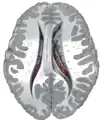

Caudate nucleus within the skull

Together with the putamen, the caudate forms the dorsal striatum, which is considered a single functional structure; anatomically, it is separated by a large white matter tract, the internal capsule, so it is sometimes also referred to as two structures: the medial dorsal striatum (the caudate) and the lateral dorsal striatum (the putamen). In this vein, the two are functionally distinct not as a result of structural differences, but merely due to the topographical distribution of function.

The caudate nuclei are located near the center of the brain, sitting astride the thalamus. There is a caudate nucleus within each hemisphere of the brain. Individually, they resemble a C-shape structure with a wider "head" (caput in Latin) at the front, tapering to a "body" (corpus) and a "tail" (cauda). Sometimes a part of the caudate nucleus is referred to as the "knee" (genu).[7] The caudate head receives its blood supply from the lenticulostriate artery while the tail of the caudate receives its blood supply from the anterior choroidal artery.[8]

The head and body of the caudate nucleus form part of the floor of the anterior horn of the lateral ventricle. After the body travels briefly towards the back of the head, the tail curves back toward the anterior, forming the roof of the inferior horn of the lateral ventricle. This means that a coronal (on a plane parallel to the face) section that cuts through the tail will also cross the body and head of the caudate nucleus.